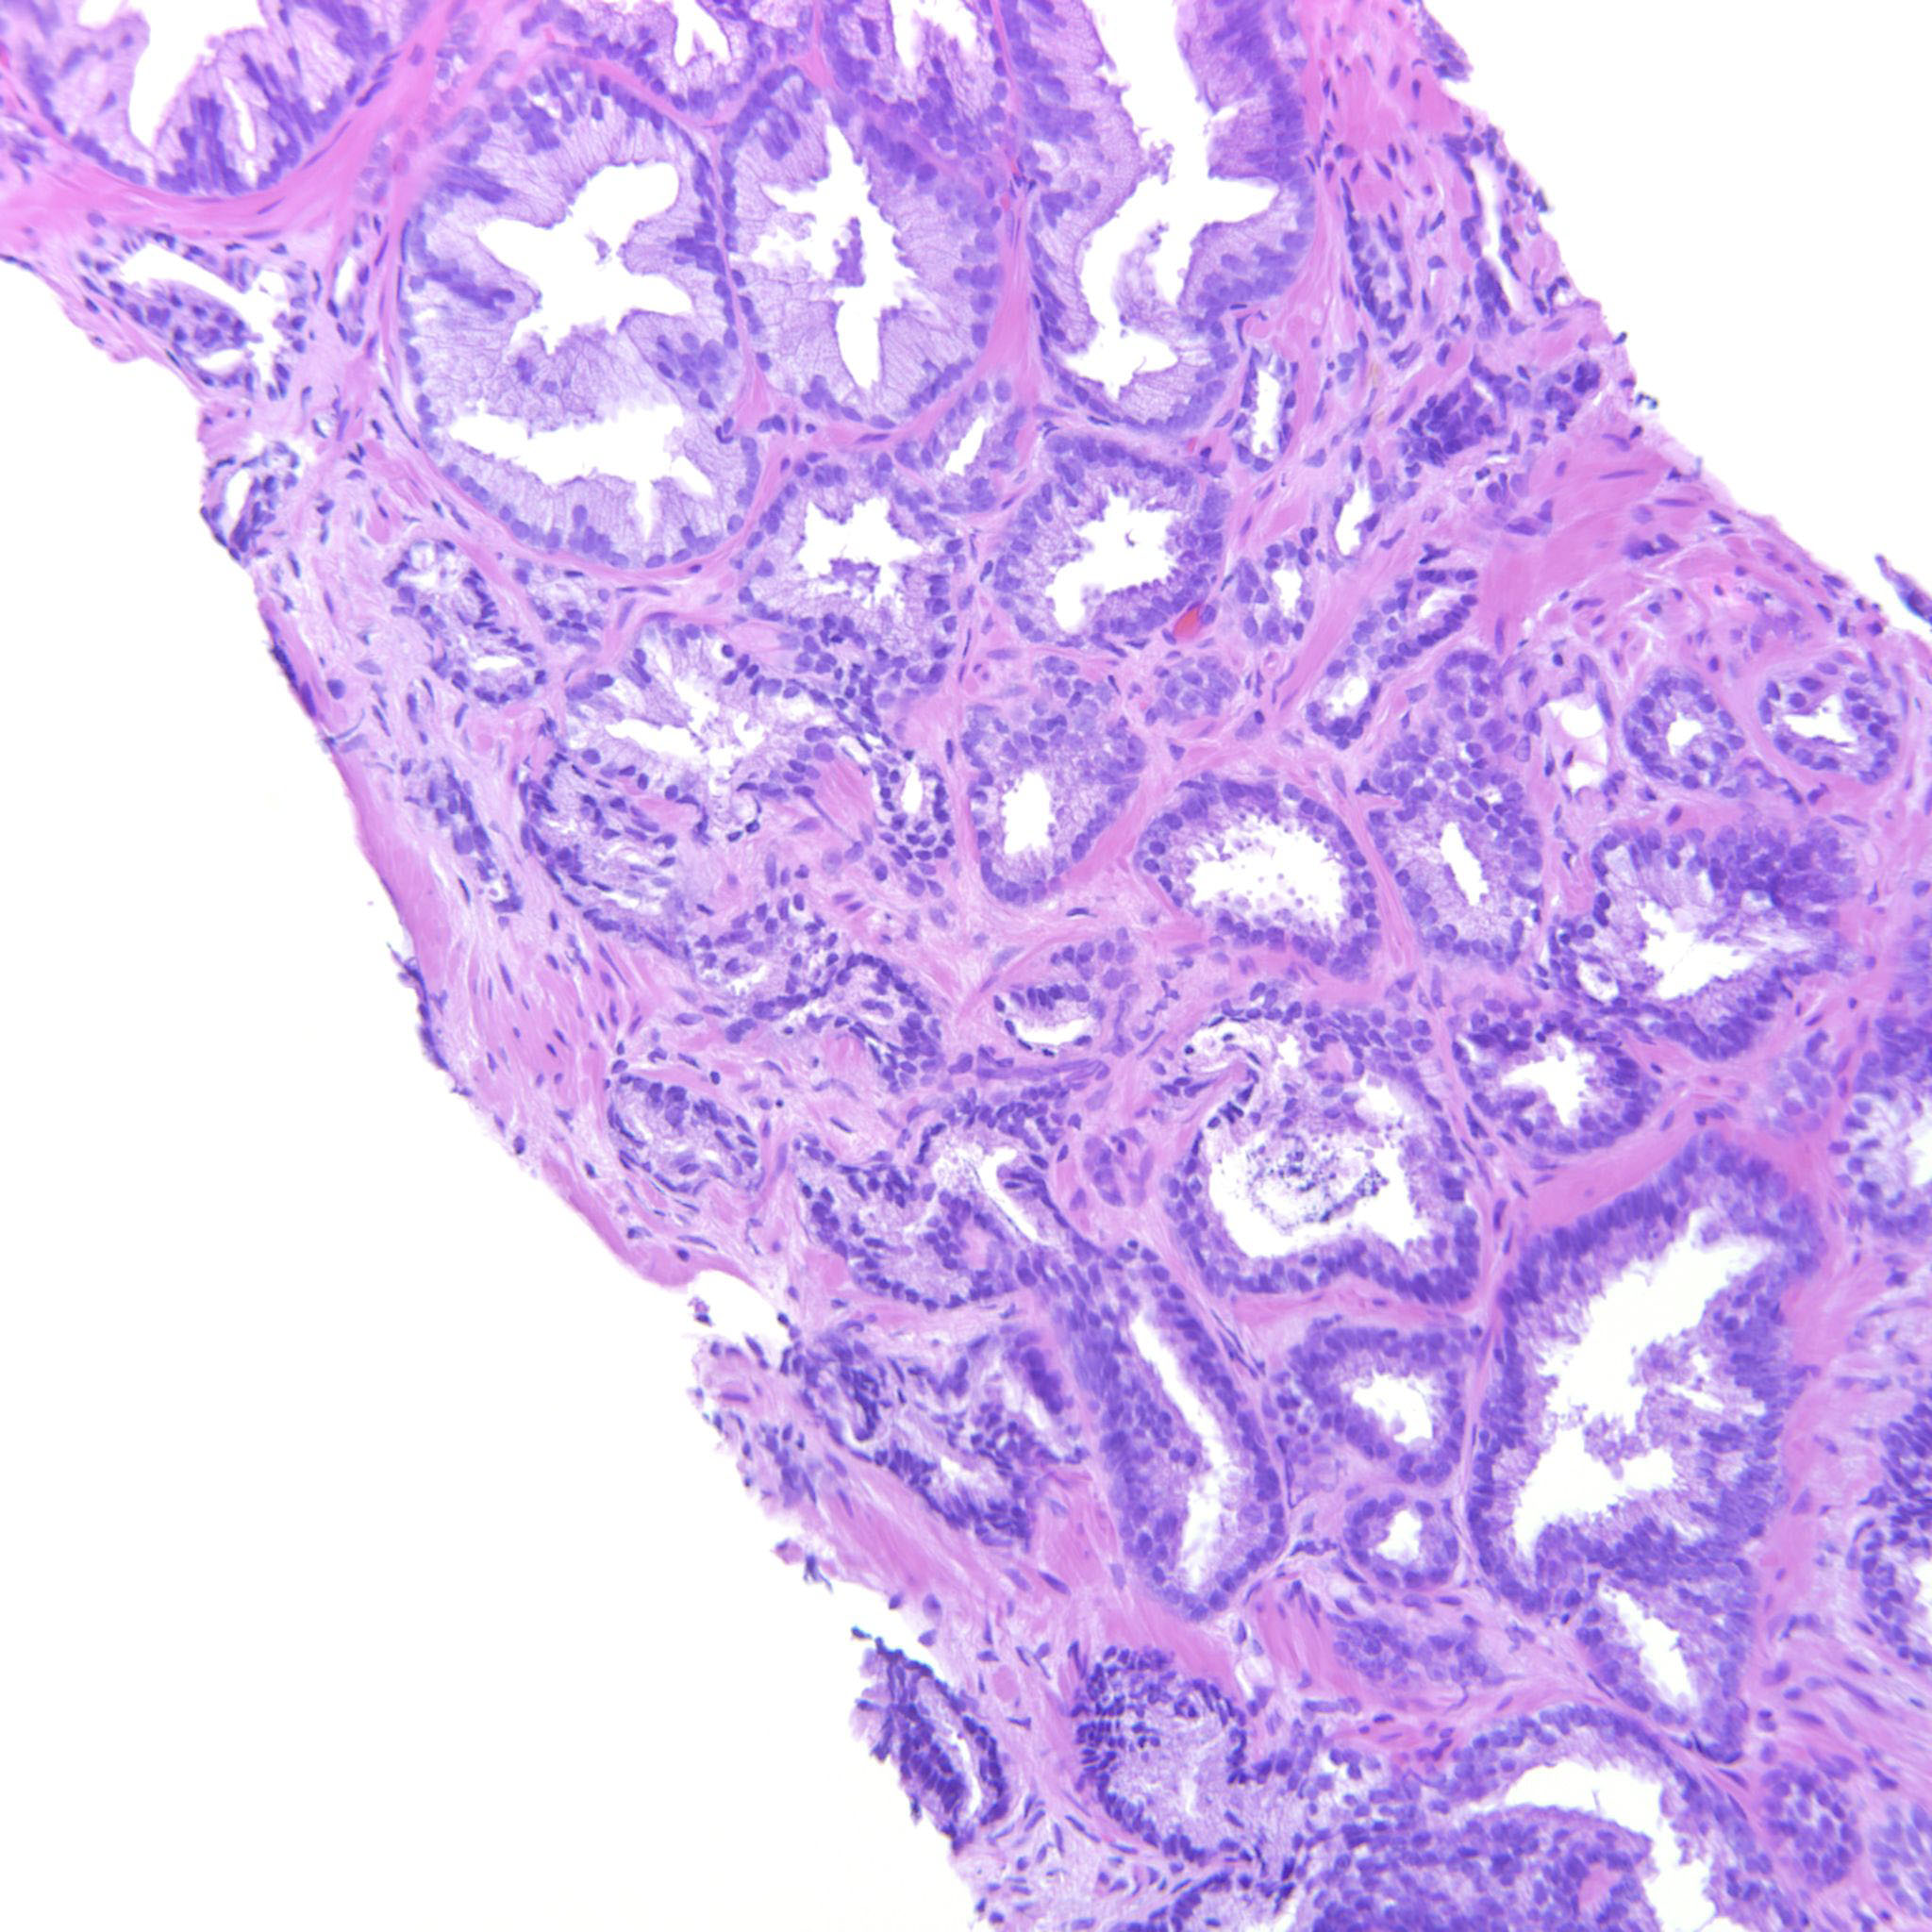

Prostate cancer grading

Case ID: 314